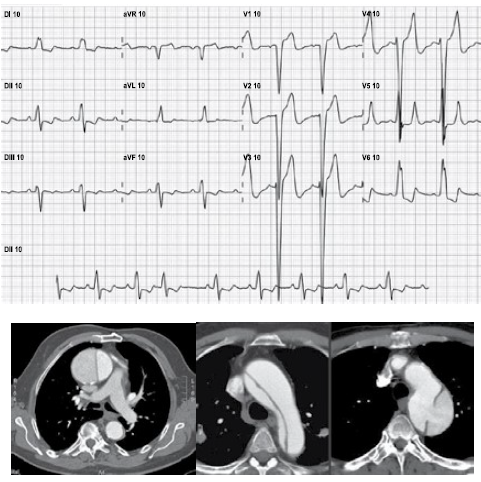

Homem, 65 anos, com histórico de hipertensão arterial, refere dor torácica retroesternal de forte intensidade e contínua,

há cerca de 1 hora, acompanhada de sudorese e mal estar. Exame clínico: ausculta pulmonar e cardíaca estão normais;

PA = 160 x 95 mmHg; FR = 20 ipm; temperatura axilar = 36,7 ºC; SpO2 = 98%. Foram realizados eletrocardiograma e

angiotomografia de tórax, que encontram-se ilustrados a seguir.

A conduta mais apropriada neste momento, deve ser: